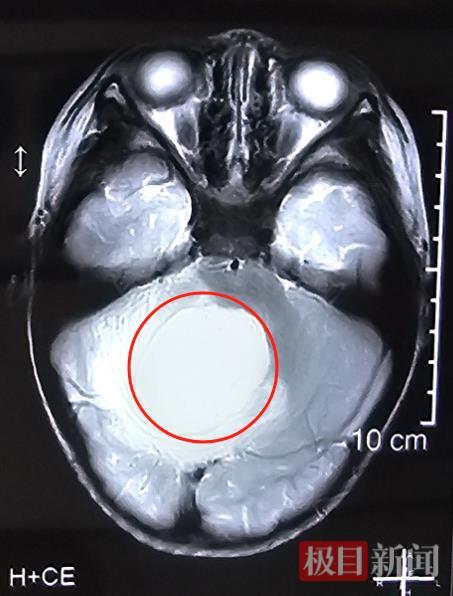

5月中旬,湖北仙桃2岁10个月的晨晨(化名)突然出现间断性的恶心呕吐。起初,家人以为只是吃坏了东西,但连日来,这样的症状不仅反复出现,还不断加重。当地医院头部磁共振检查显示“脑干背侧、四脑室巨大肿瘤性病变”,同时伴有脑积水,考虑恶性髓母细胞瘤可能性大,病情非常严重。为寻求一线生机,一家人慕名找到武汉大学人民医院神经外Ⅲ科副主任徐海涛教授。

入院后,徐海涛教授团队迅速组织多学科会诊,并进行了详细的术前评估与准备。由于第四脑室解剖结构复杂,底部为人的“生命中枢”脑干,手术操作必须非常细致和精准,稍有不慎就有可能出现术后昏迷、瘫痪、呼吸衰竭甚至死亡的严重后果,手术风险大且难度高。但患儿病情进展快,如果不尽快手术切除,肿瘤对脑干的压迫会逐渐加重、危及生命。与患儿家长充分沟通后,家长决心放手一搏。